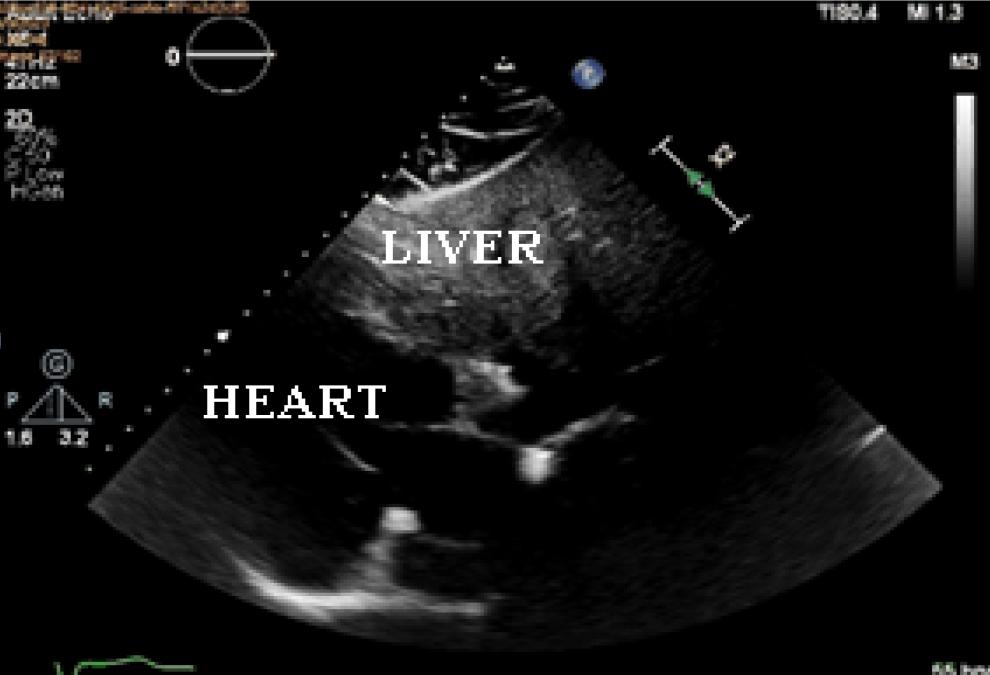

Figure 1